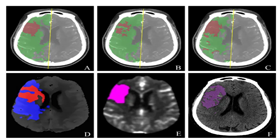

已应用于西医医疗设备医疗诊断和中医诊断,,为诊疗提供辅助决策支持。。。。